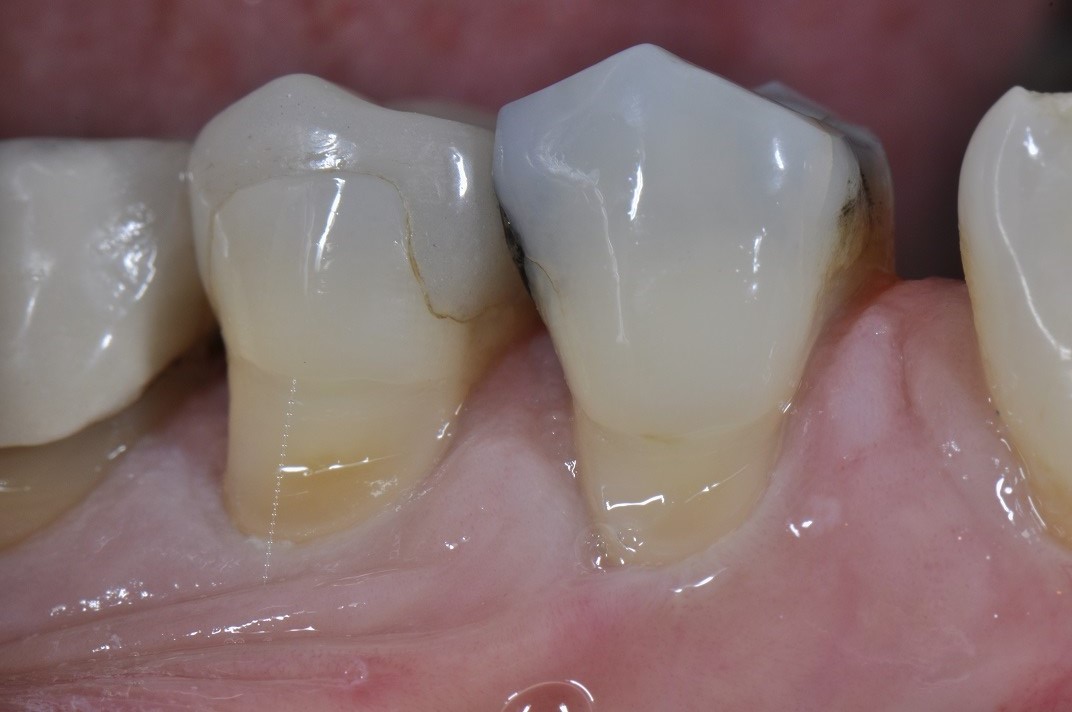

Root abrasion lesions restored and protected

Root abrasion lesions restored and protected What Is Abrasion In Dental   tooth abrasion is a form of tooth wear that is caused by the repetitive grinding or scrubbing of the teeth against a hard surface.   tooth abrasion is where your teeth start to lose enamel due to some sort of outside. Dental abrasion is a condition that occurs when the tooth enamel wears away due to external factors. . What Is Abrasion In Dental.